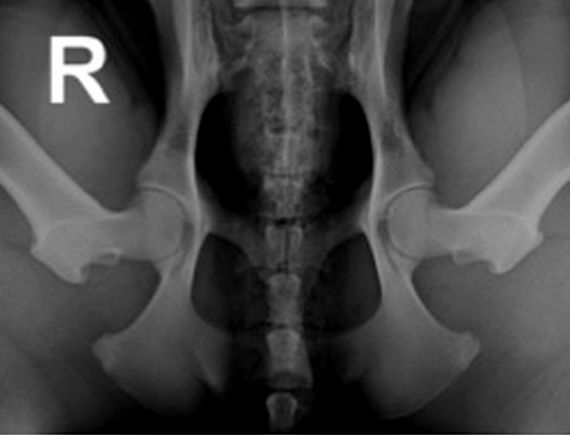

Für das PennHIP® Verfahren werden drei Röntgenaufnahmen angefertigt:

Bei der Distraktionsaufnahme wird ein sogenannter Distraktor zwischen die Beine des Tieres gelegt. Wenn der Untersucher die Beine des Hundes gegen den Distraktor drückt, wird der Oberschenkelkopf aus der Hüftpfanne „herausgezogen“. Je weiter das möglich ist, desto lockerer ist die Hüfte und desto größer die Wahrscheinlichkeit, dass ein Hund an einer HD leiden wird. Das Maß für die Lockerheit des Hüftgelenks ist dabei der Distraktionsindex (DI).

links: komprimiertes Hüftgelenk

rechts: distrahiertes Hüftgelenk

Der Distraktionsindex wird berechnet, indem bei der Distraktionsaufnahme die Entfernung zwischen dem Mittelpunkt des Oberschenkelkopfes und dem Mittelpunkt Hüftpfanne gemessen und diese Strecke durch den Radius des Oberschenkelkopfes geteilt wird. Dabei kann der Index von 0 bis 1,0 betragen. Bis zu einem Distraktionsindex von 0,3 ist die Wahrscheinlichkeit, dass sich das Krankheitsbild einer HD entwickelt, äußerst gering. Bei Rassen wie z.B. dem Barsoi oder dem Greyhound ist ein solcher DI üblich. Bei diesen Rassen entwickelt sich im Verlaufe des Lebens im Regelfall nicht das Krankheitsbild einer HD.